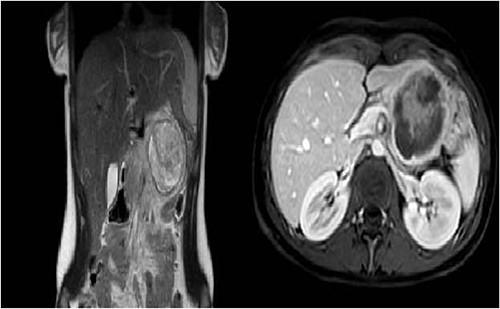

In March 2022, a 17-year-old female with no past medical history was admitted to the Emergency Department with a 5-day history of recurring central quadrant pain and several episodes of emesis. At physical examination, she revealed a non-distended abdomen with minimal tenderness in the central quadrant. Ultrasound showed a well-circumscribed hypoechoic lesion measuring 6.5 cm in diameter near the left hepatic lobe.

The patient was referred to the Haematology Department and underwent an MRI that showed features consistent with a diagnosis of SPT. After surgical evaluation, the patient was referred to our Department. Preoperative workup included also a thoraco-abdominal CT-scan and normal levels of pancreatic tumour markers (chromogranin A, CA19.9, CA125) (Fig. 1).